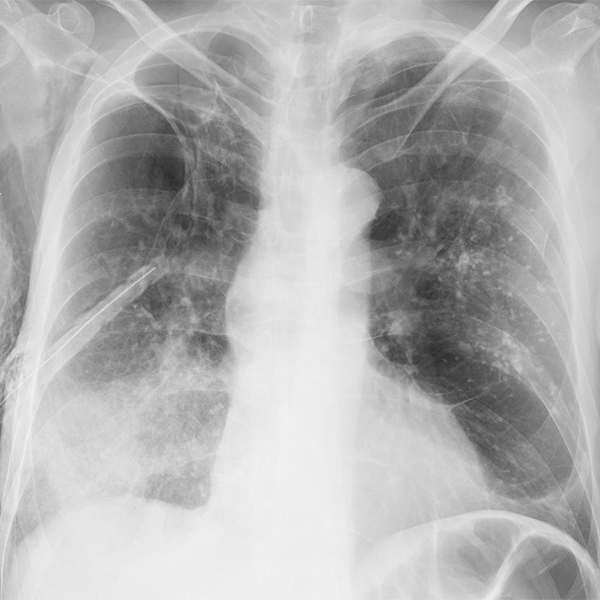

肺不张

左下肺盘状肺不张

【x线诊断要点】关于"肺不张",需要弄清楚以下几点